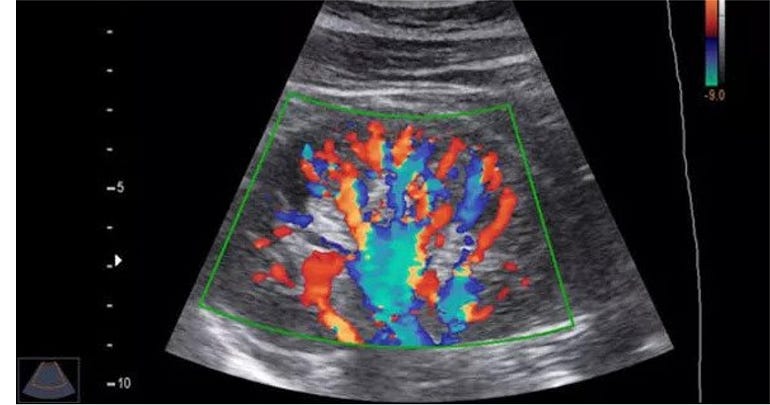

A Colour Doppler Ultrasound is a specialized imaging technique that uses sound waves to visualize blood flow within the body’s blood vessels. Unlike a standard ultrasound that only produces black-and-white images, a Colour Doppler ultrasound adds color to show the speed and direction of blood flow. This advanced technology helps in the diagnosis and monitoring of various medical conditions, providing critical insights into your health.

Colour Doppler Ultrasound